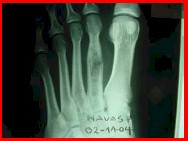

FIBROMA CONDROMIXOIDE:

Tienen contenido. Se da en rodilla y calcáneo.. En la segunda década de la vida. Es excéntrico. Borde esclerótico. Lobulado.

Figura 9: fibroma condromixoide